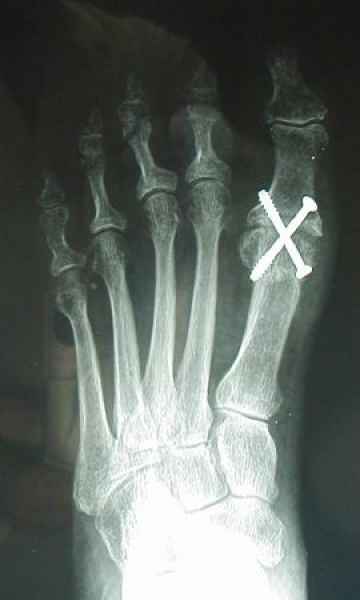

Tanto la estructura del pie como su funcionalismo que es la marcha, pueden ser asiento y manifestación respectivamente de alteraciones locales ó sistémicas, por lo que su cuidadoso examen resulta de extrema utilidad diagnóstica.